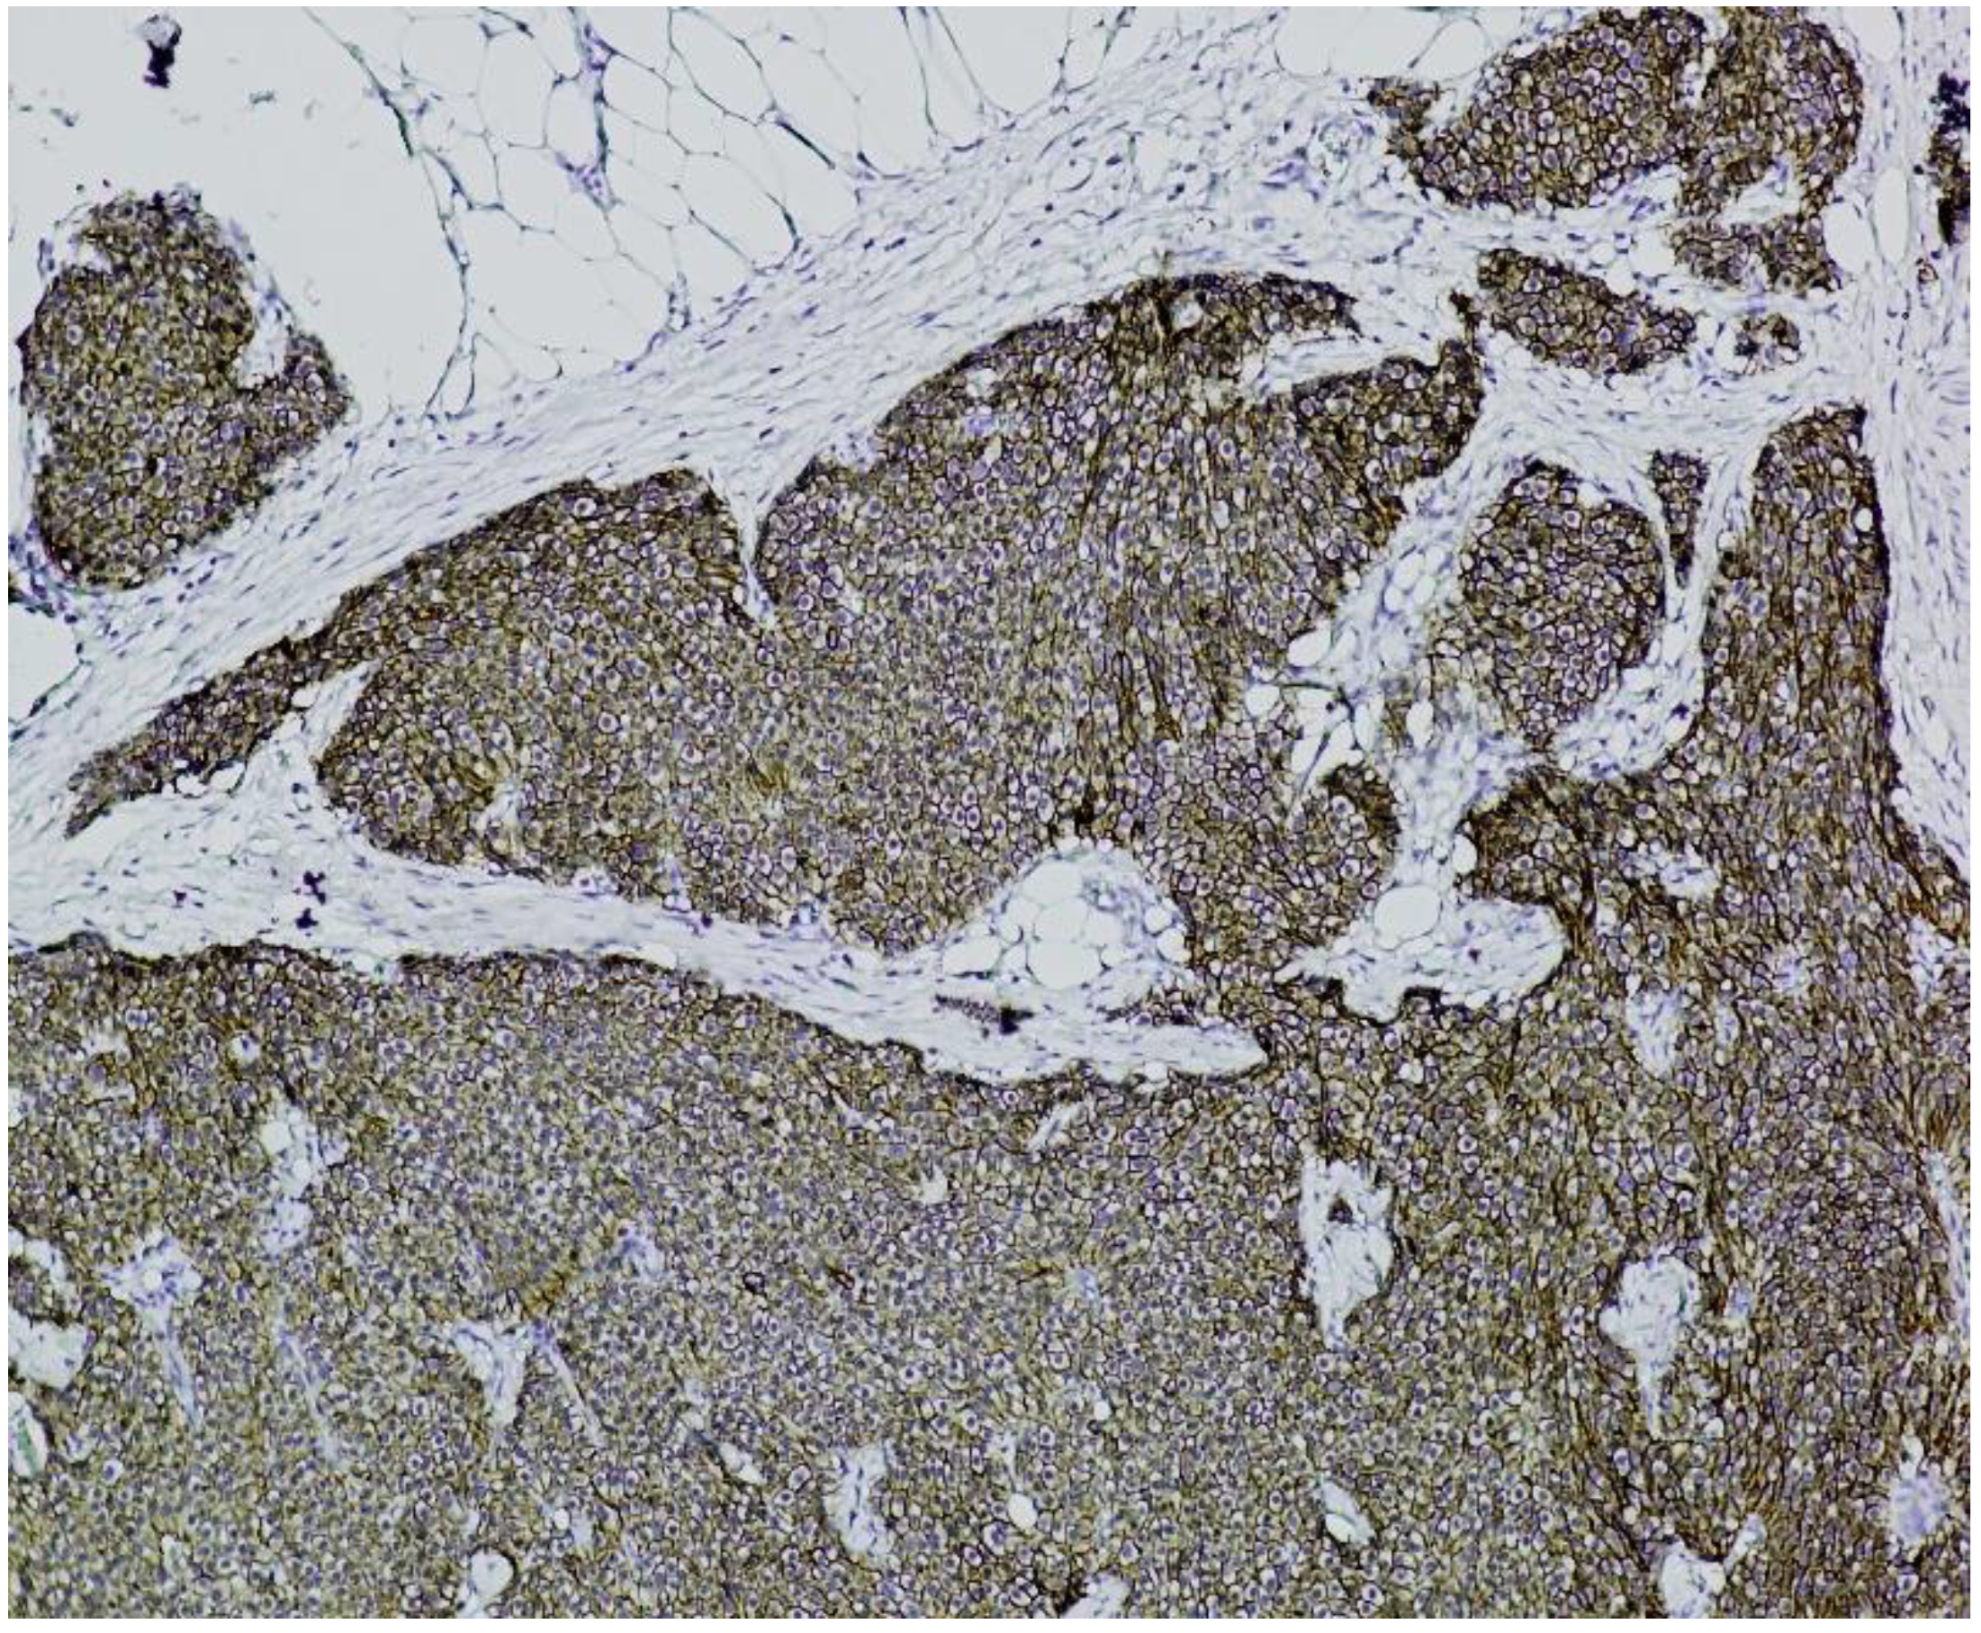

Immunohistochemistry (IHC) showed diffuse and strong positivity for chromogranin A and CD56, with focal weak staining for synaptophysin, supporting neuroendocrine differentiation (Figure 5, Figure 6, Figure 7 and Figure 8).

Figure 5. Chromogranin A immunostaining (×100). Diffuse and strong cytoplasmic staining is observed in nests of uniform neuroendocrine tumor cells, confirming neuroendocrine differentiation.